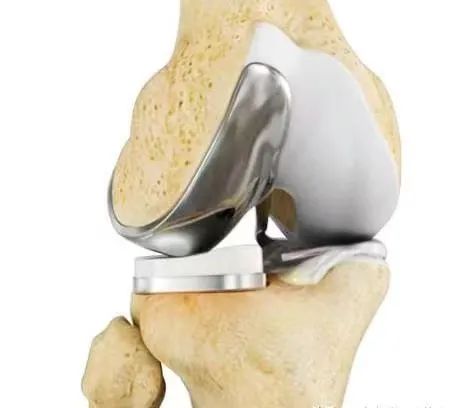

膝关节外侧单髁置换适应局限于外侧单间室的骨关节炎,尹一然副教授介绍,作为一种保膝治疗手段,相对于全膝关节置换而言是一种微创术式。

对膝关节内侧或外侧间室进行表面置换,用以替代膝关节胫、股骨损伤的软骨,被称为膝关节置换中的“补牙”技术,也可以理解为只换“一半关节”。该技术不需要去除膝关节内的前后交叉韧带,最大限度的保留了患者的本体感觉和关节功能。